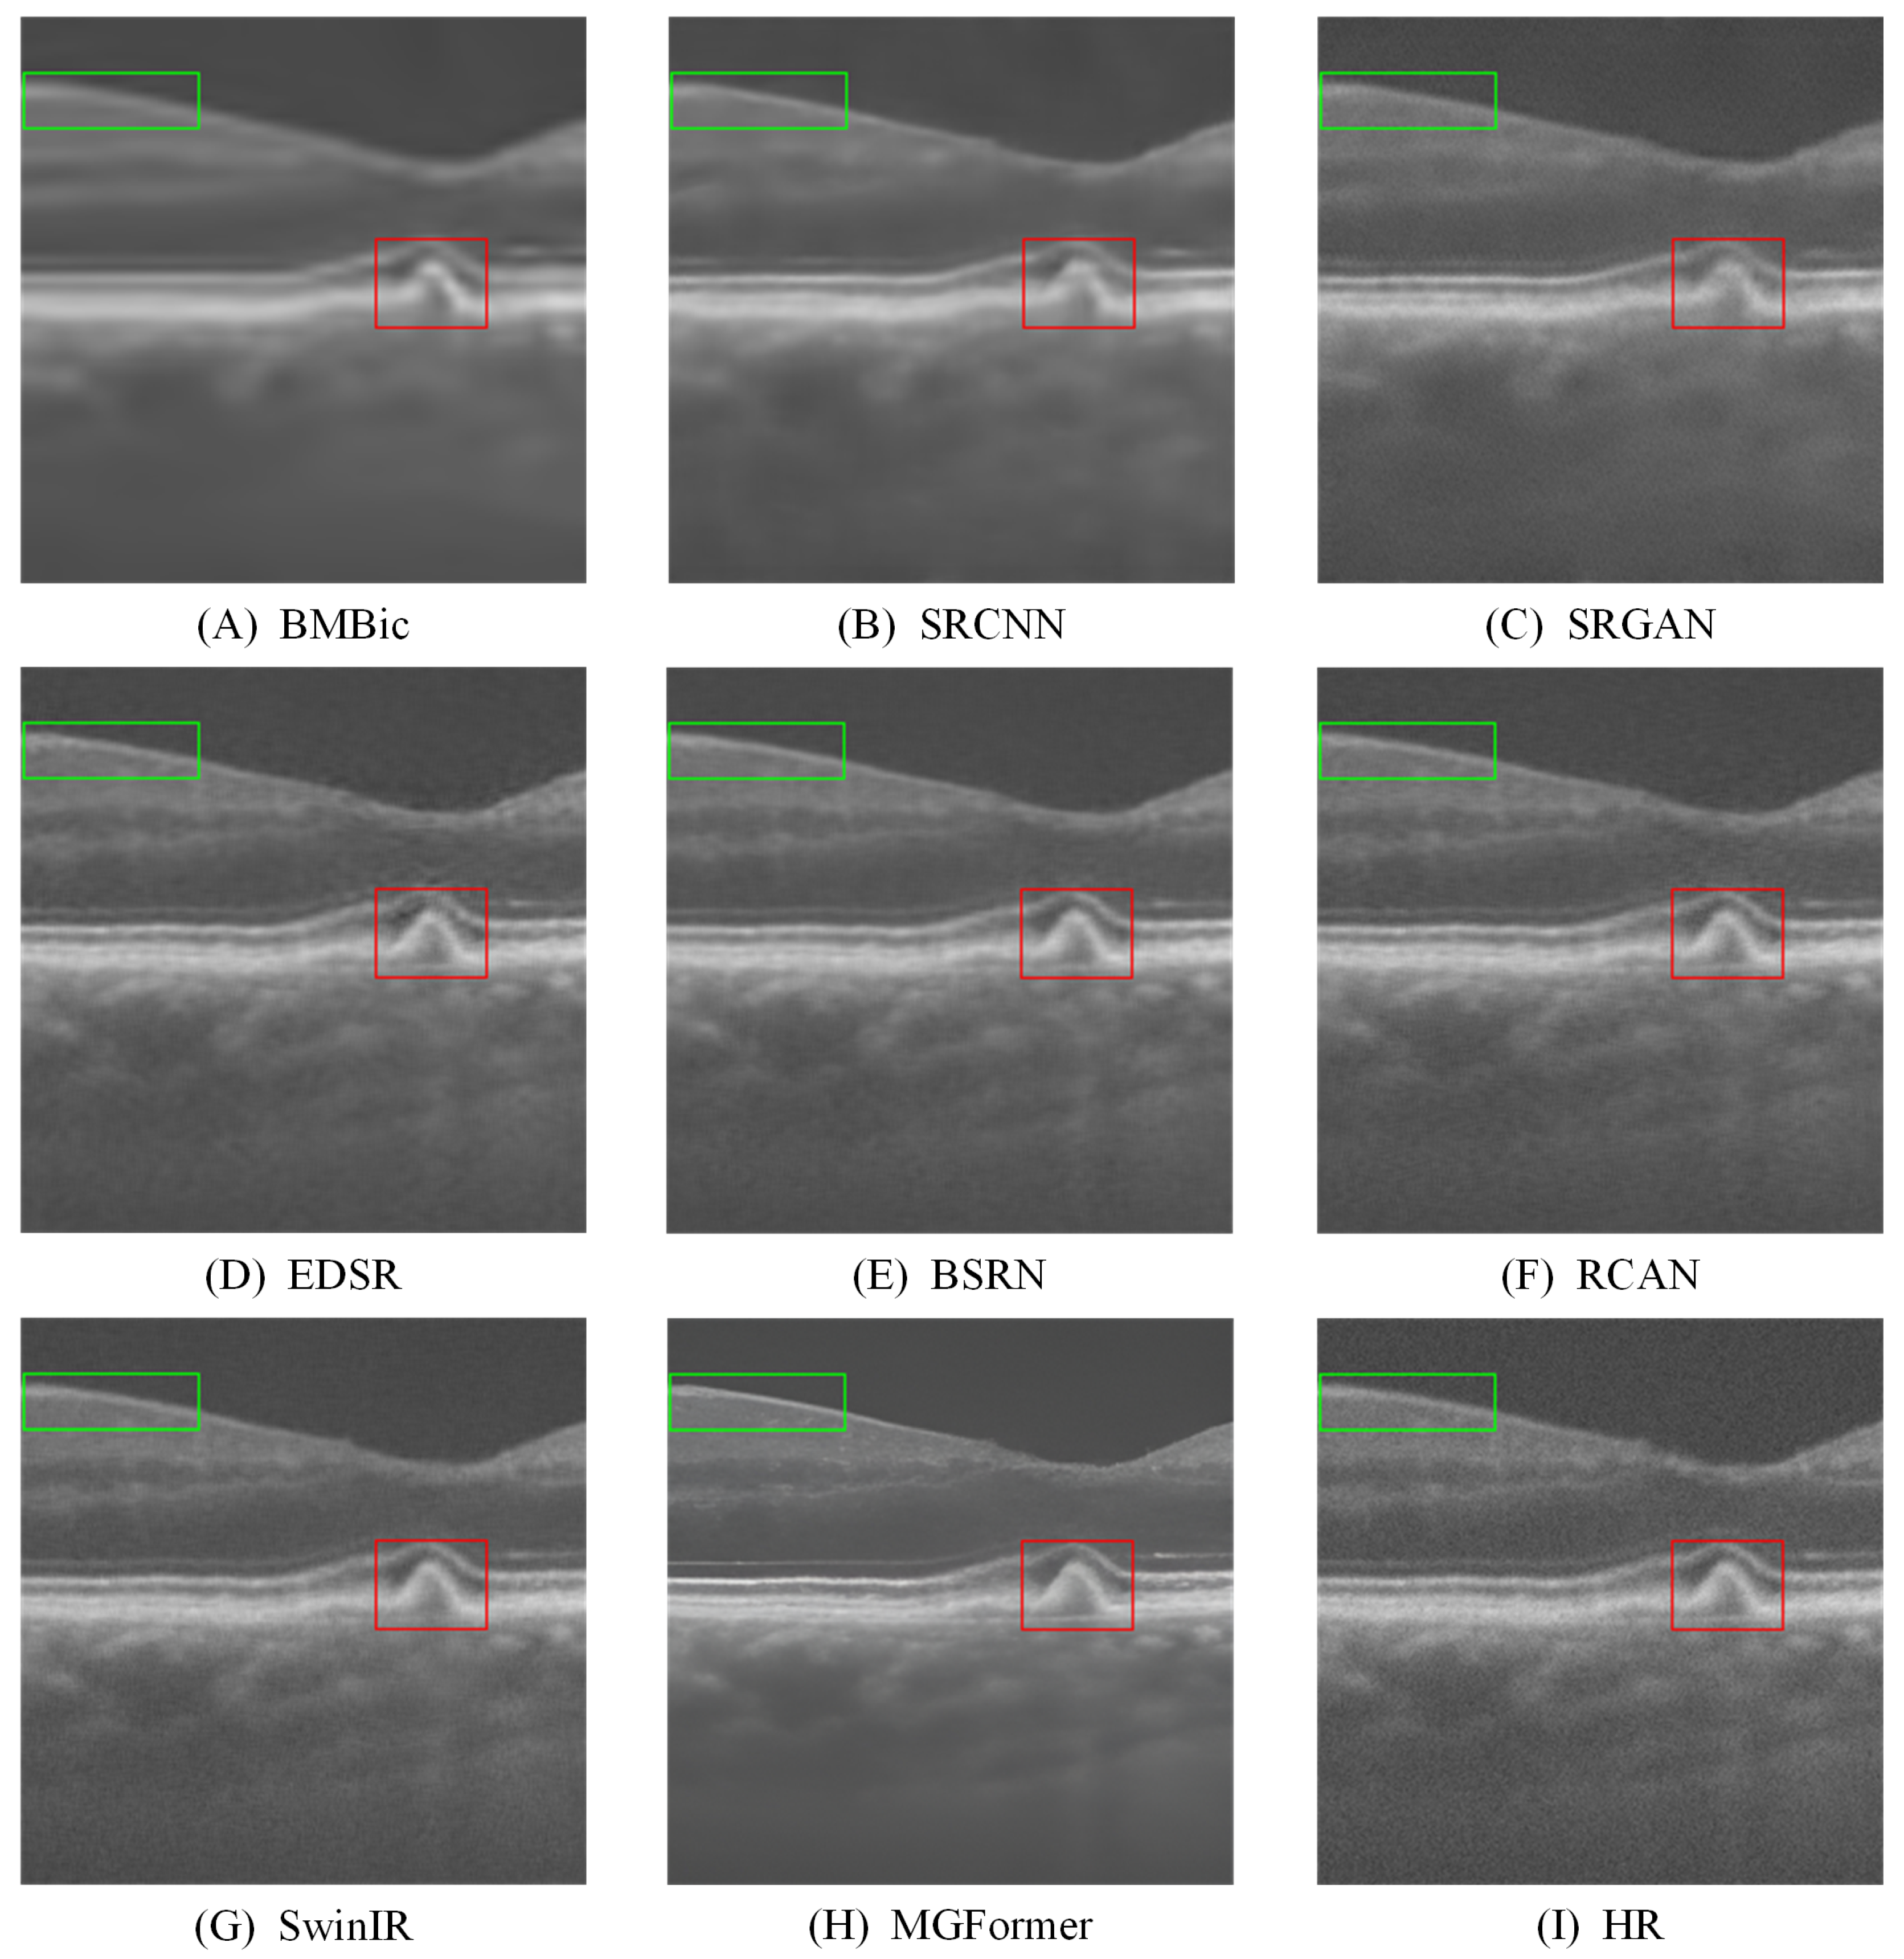

- Extensive experiments on both benchmark and clinical OCT datasets demonstrate that MGFormer consistently outperforms state-of-the-art SR models, including SRCNN, SRGAN, EDSR, BSRN, RCAN, and SwinIR, in terms of both quantitative metrics (PSNR, SSIM, and LPIPS) and qualitative visual assessment.

| BMBic | 2.5 ± 0.3 | 2.3 ± 0.3 | 2.4 ± 0.2 |

| SRGAN | 3.4 ± 0.5 | 3.2 ± 0.6 | 3.3 ± 0.5 |

| SwinIR | 3.9 ± 0.4 | 3.7 ± 0.3 | 3.8 ± 0.3 |

| MGFormer | 4.2 ± 0.3 | 4.1 ± 0.3 | 4.3 ± 0.2 |